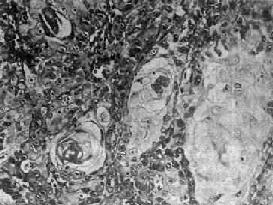

(1)鳞状细胞癌:高分化鳞状细胞癌的癌巢细胞分层明显,可见清晰的棘细胞及细胞内角化,有的还可见角化珠(图9-3)。低分化鳞状细胞癌的癌巢细胞分层多不明显,癌细胞呈多角形、卵圆形、梭形或不规则形,胞浆丰富,境界清楚,少数细胞可见细胞间桥,但无角化现象。

图9-3 鼻咽高分化鳞状细胞癌

癌细胞分化成熟,有角化珠形成